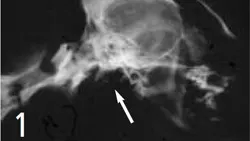

2. Normal feline tympanic bulla. Air shadow from external ear canal is superimposed on tympanic bulla.